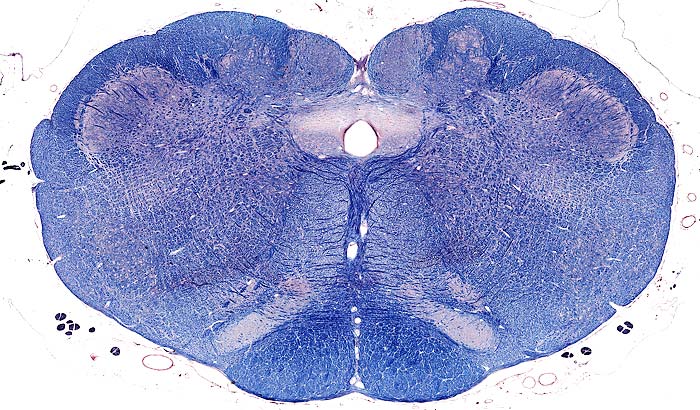

Myelencephalon

pyramidal tract

medial lemniscus

central canal

obex

nucleus gracilis

medial cuneate nucleus

fasciculus cuneatus

spinal tract of V

nucleus of spinal tract of V

nucleus ambiguus

reticular formation

olivary nucleus

cranial nerves

hypoglossal nerve

spinal root of accessory nerve

Transection: Nucleus Gracilis & Medial Cuneate Nucleus